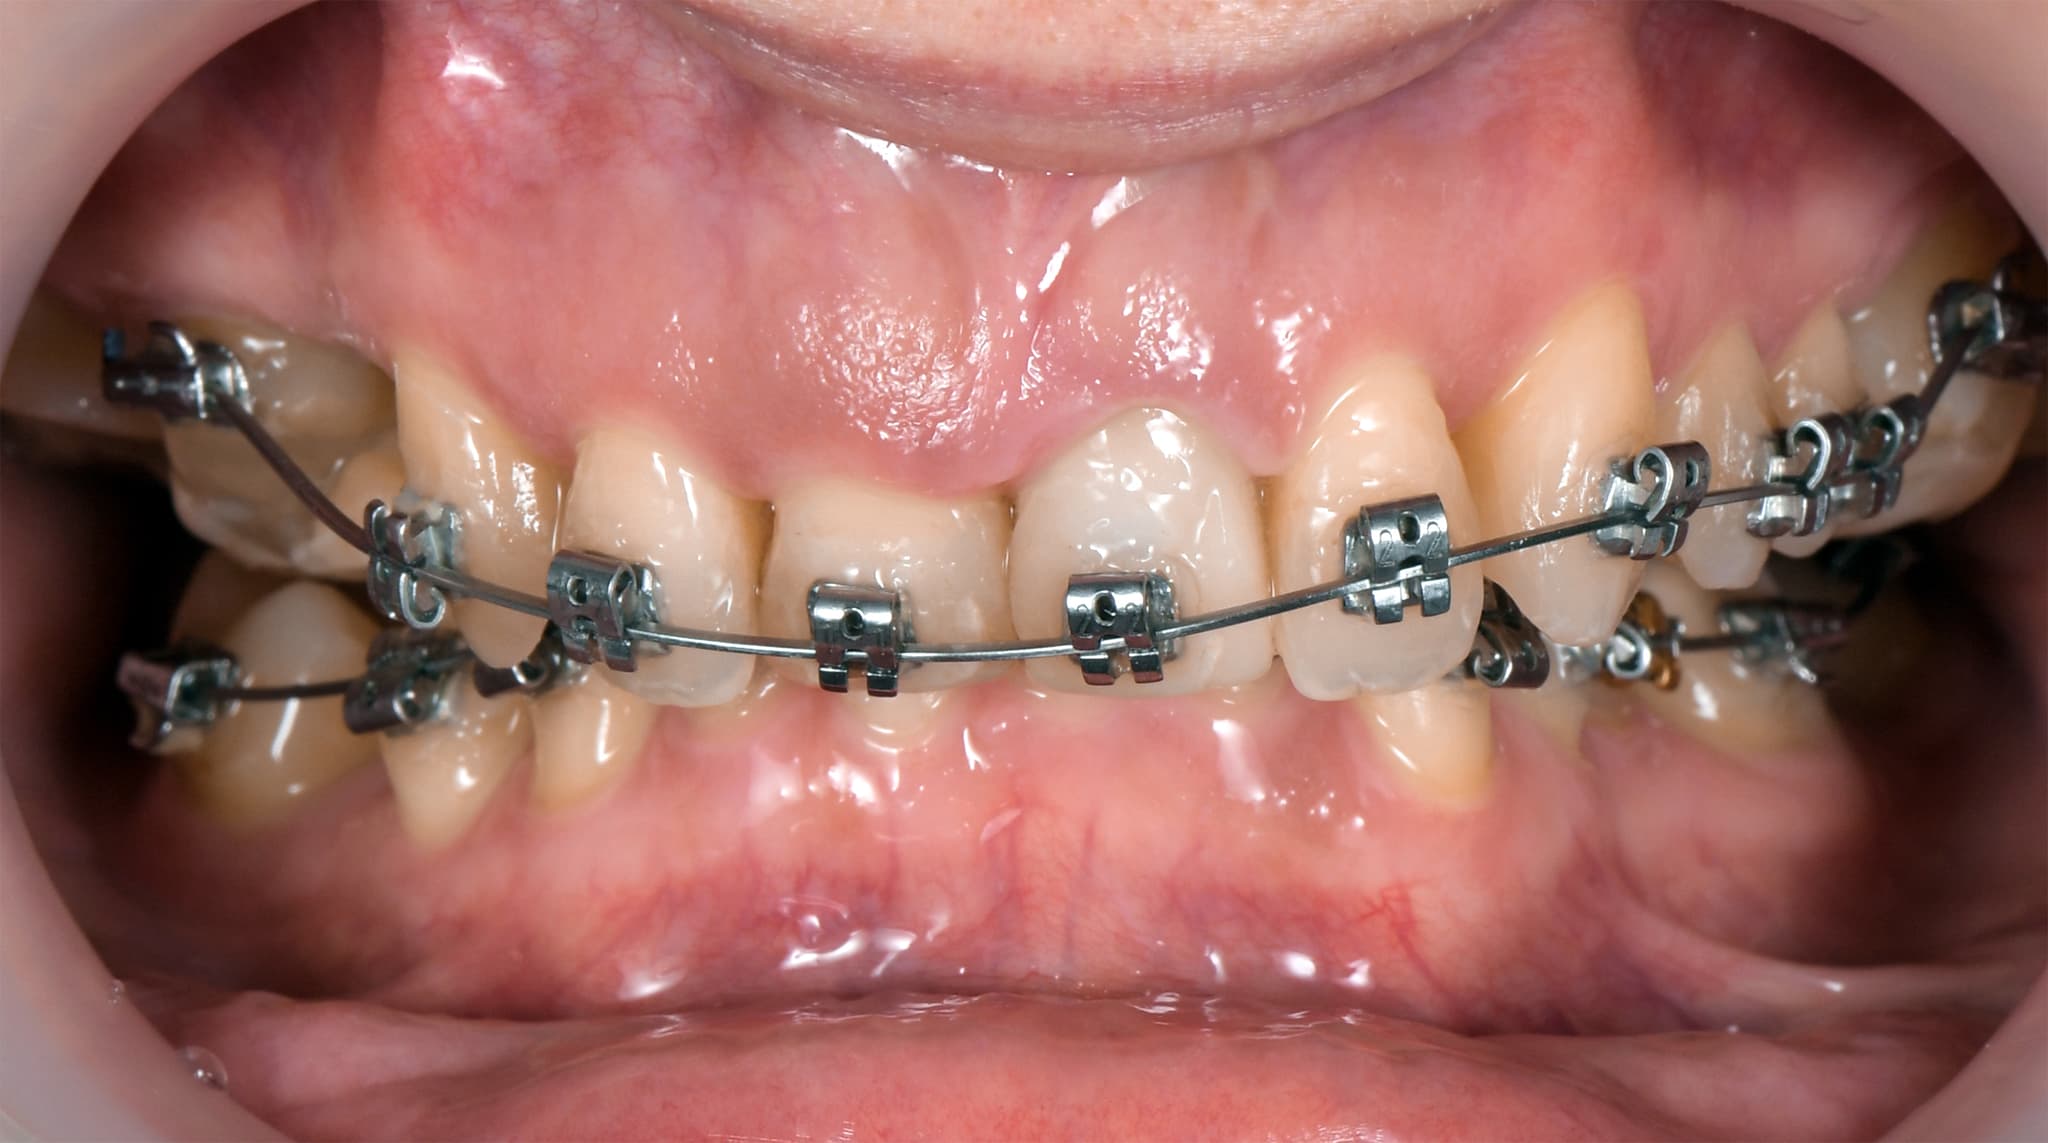

După validarea planului, începem faza activă a tratamentului. Fie că folosim alignere sau aparate fixe, fiecare pas este ghidat de designul final. Mișcăm dinții pentru a reduce nevoia de intervenții protetice, aliniem nivelurile gingivale pentru un rezultat estetic viitor și, uneori, folosim implanturi ca puncte de ancorare pentru a obține rezultate mai rapide și mai eficiente. Obiectivul este să reducem intervențiile invazive și să maximizăm sinergia.